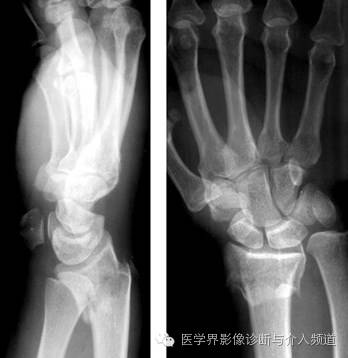

6、Colles 骨折

桡骨远端横形骨折。骨折线位于干骺端,邻近关节,远折端向背侧移位,断端向掌侧成角,通常伴尺骨茎突骨折。受伤机制为摔倒时候手撑地成过伸状。

7、Smith骨折

桡骨远端横形骨折,又称反Colles骨折。骨折线位于干骺端,邻近关节,远折端向掌侧移位,断端向背侧成角,通常伴茎突骨折。受伤机制摔倒时候手撑地呈过屈状。